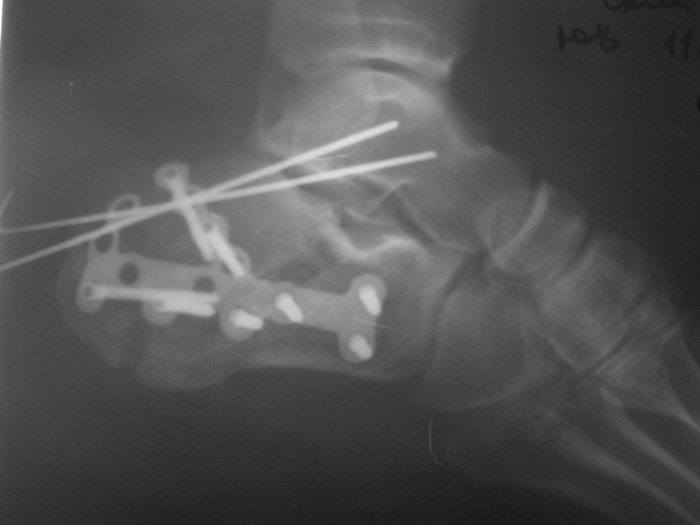

Операция проведена на 14е сутки после травмы. Фиксация блокируемой пластиной. Трудности - сложность репозиции; необходимость костной пластики (уложен измельченный трансплантат из гребня подвздошной кости 4,5х1,5х1см); множество мелких отломков; большой фрагмент наружной кортикальной пластинки, закрывающий картину в суставе.